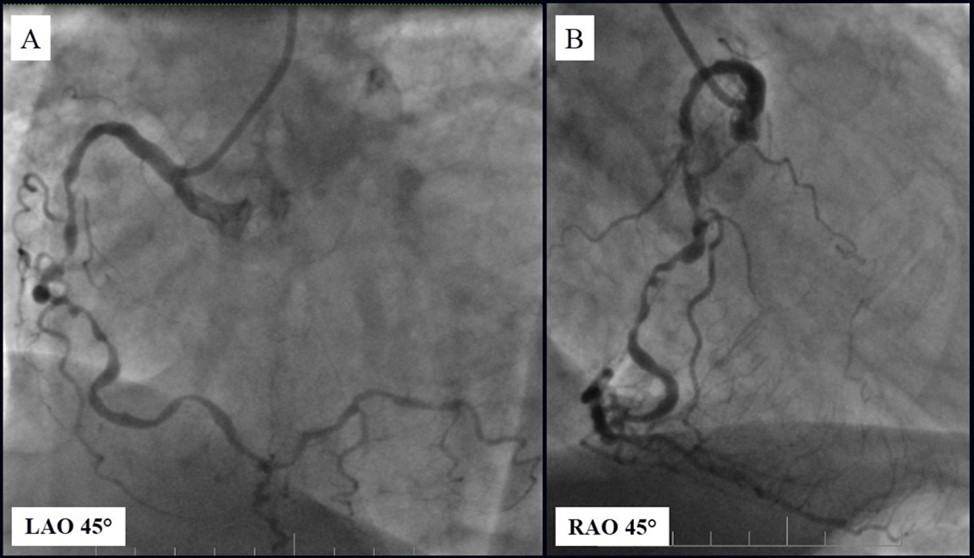

Angiography revealed rare anatomical variation LMCA quadrifurcation (Figure 1, Figure 2), 50% stenosis of the distal part of the LMCA, 40% stenosis of the ostial segment of left anterior descending (LAD) artery and diffuse prolonged 70-75-95% stenosis in mid-segment (Figure 3), 75% stenosis of the ostial segment of the circumflex (CX) artery, 75% stenosis of the ostial segment of the first marginal branch (OM1), 75-90% stenosis of the proximal segment of the intermediate artery (IMA), prolonged diffuse severe 90-95% stenosis of mid-segment of the right coronary artery (RCA) (Figure 4).

Figure 4.A - 50% stenosis of the distal segment of the LMCA; B - 70-75-95% stenosis in mid-segment of the LAD.

A - 50% stenosis of the distal segment of the LMCA; B - 70-75-95% stenosis in mid-segment of the LAD.